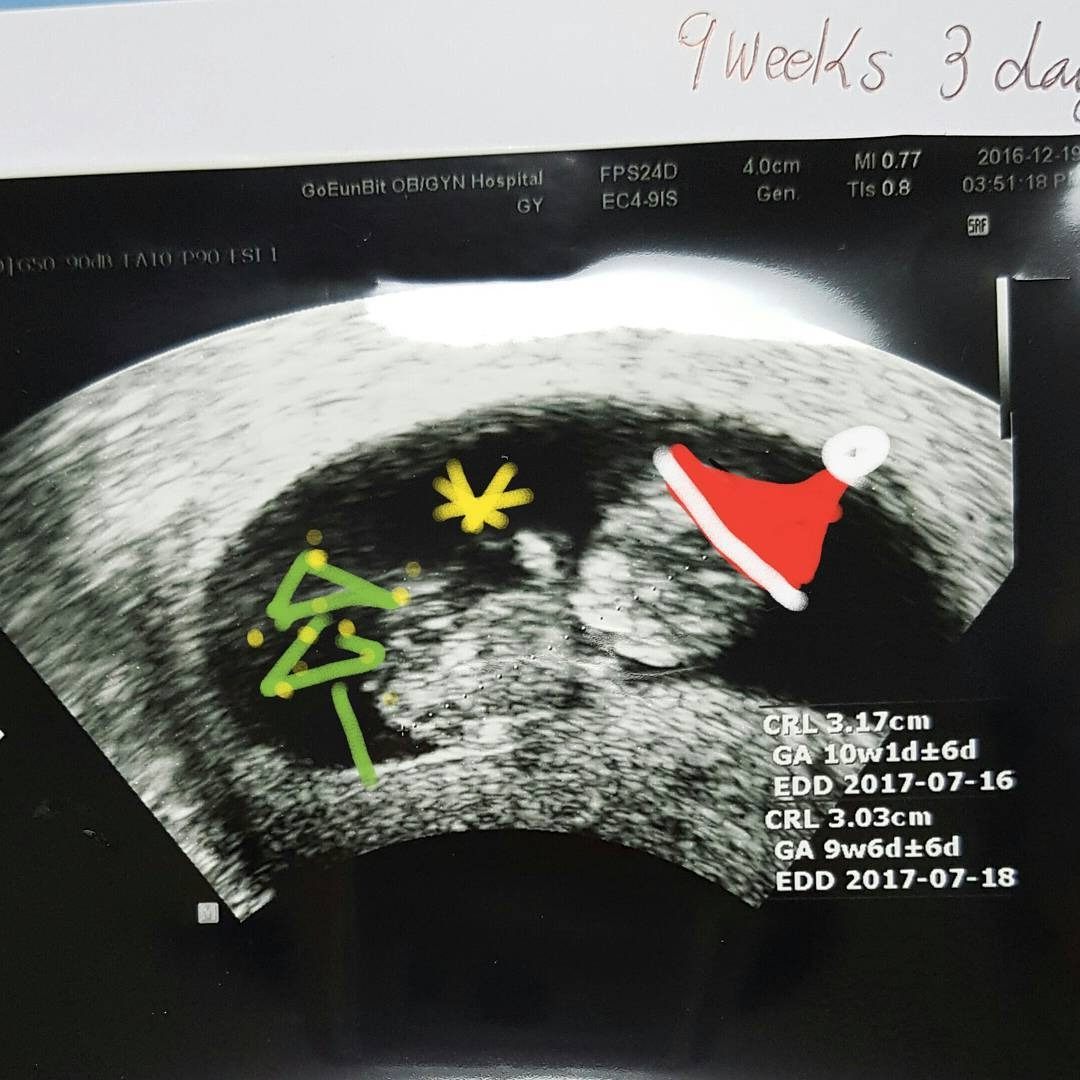

아이 곱하기 아이 <슈퍼문과 크리스마스>

<슈퍼문과 크리스마스>

그렇게 겨울은 달처럼 차올라 갔고 연말이 되어 크리스마스 시즌이 되었다. 성당의 아기 예수 조각상이나 그림을 관찰하면 어머니나 아버지 품에 안겨있는 모습들이 많다. 그 모습을 그리기 위해 천진하게 안겨있는 아기들을 예술가들은 마음에 아로새겼겠지. 내 아이도 내 품에서 저렇게 기분 좋게 웃을 수 있게 나는 어떤 사람이 되어야 할 것일까? 크리스마스 자체가 아기 예수의 탄생을 기리기 위해 풍성해진 축제이기 때문에 내 아이의 잉태도 더불어 축하하는 기분으로 즐겁게 작은 트리 벽장식도 달고 캐럴송도 들으며 틈틈이 신을 향해 기원을 했다. 곧 태어날 생명을 위해 내가 해 줄 수 있는 가장 무한한 것은 긍정적인 응원과 기원이겠지. 때때로 비관적이고 시니컬한 나의 성격이 금방 바뀌지는 않겠지만 좀 더 넓은 바다처럼 마음을 펼칠 수 있는 성장의 계기가 되기를 바란다.